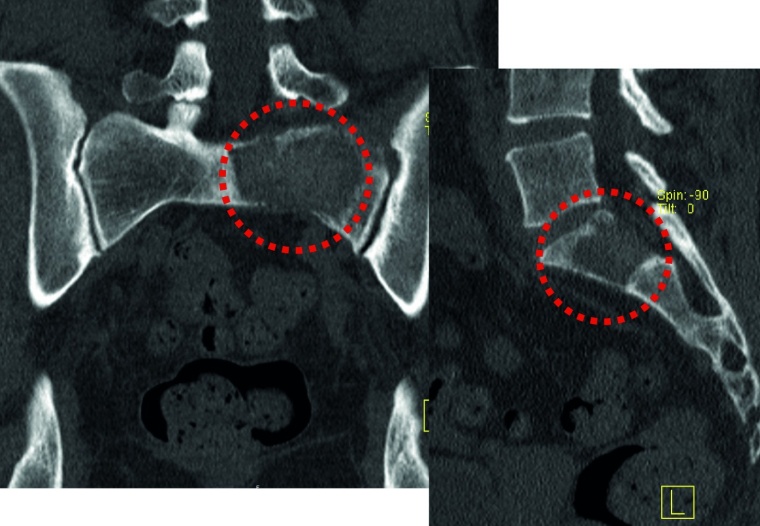

Fixateur interne: Haben die Osteolysen bereits Frakturen verursacht und weisen die betroffenen Wirbelkörper relevante Deformitäten auf, hat sich die perkutane überbrückende Stabilisierung mittels Fixateur interne bewährt (Abb. 2a und b). Der betroffene Wirbel kann ggf. additiv kyphoplastiert werden. Angesichts der sich zumeist anschließenden Radiatio verzichten wir jedoch zumeist darauf. Die Schrauben können je nach Knochenqualität zur Erhöhung der Stabilität wie üblich auch zementaugmentiert werden.